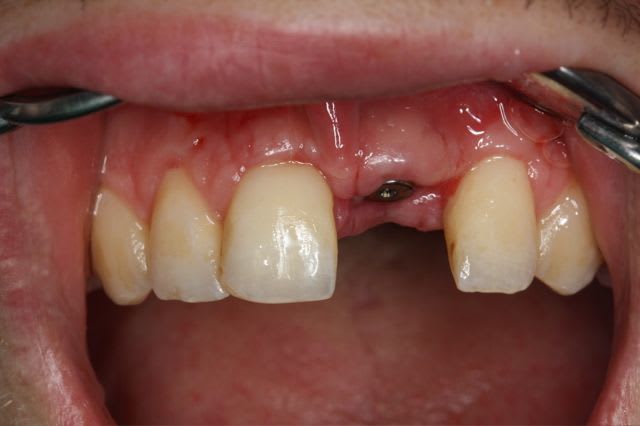

Pour le fun ! car pas bcp de photos en ce moment sur nonol

la dent était absente depuis 8 ans suite à "accident" de la vie (à 5h du mat'...)

très classiquement:

greffe onaly,

dépose des vis et pose de l'implant à 5mois1/2 avec un cj roulé et mise en place de la vis de cica,

et 3 mois 1/2 après empreinte

15j après essayage pilier et biscuit, visite au labo pour "finition en bouche" et 3 h après scellement.

en temporisation, la vieille PAP du patient (raison €€€ )